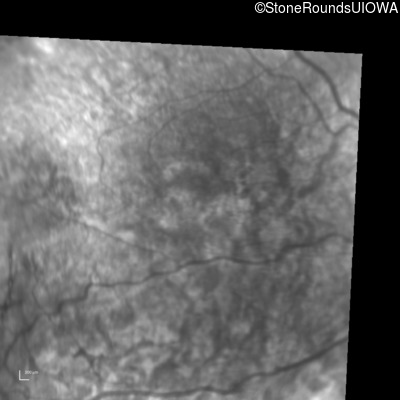

Infrared Fundus Photograph - Right - 20/63 +2

Exemplar